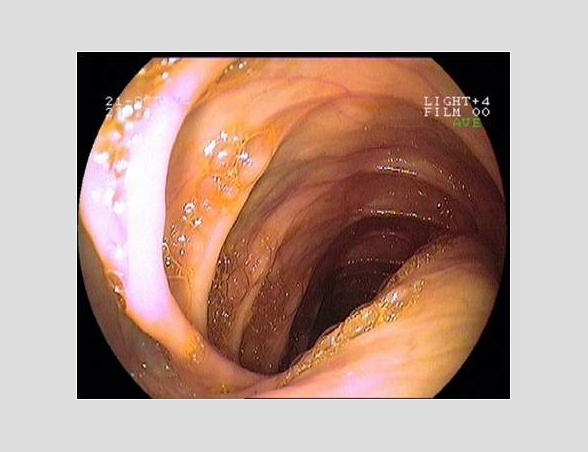

Imágenes tomadas durante la endoscopia digestiva alta y la colonoscopia. Se aprecia una mucosa de aspecto y vascularización normal, sin lesiones visibles. Se progresa con el colonoscopio hasta el íleon. Todo resulta macroscópicamente normal. Se toman biopsias de todos los segmentos explorados.

La endoscopia es el método de elección para el diagnóstico y seguimiento de la EII. Permite una visión macroscópica de la mucosa intestinal y la toma de múltiples biopsias para el estudio histológico.

Realizamos una endoscopia digestiva alta y una colonoscopia a la paciente con toma de biopsias, obteniendo el informe de Anatomía patológica.